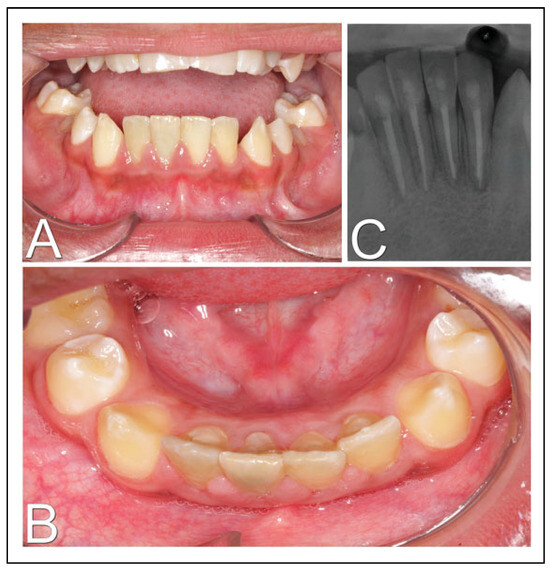

A 10-year-old male and systemically healthy patient received emergency care at the hospital, for having fallen from his own level. In the intraoral examination, bleeding, gingival laceration, severe mobility and lingual displacement of the lower incisors were found, with exposure of the dental apexes and severe pain complaints. The fractured block was only attached to the lingual gingival tissue (Figure 1A). In a tomographic evaluation, it was possible to observe an alveolar process fracture of the lower incisors (Figure 1B and C). In emergency care, with local anesthesia, the wounds were sutured and the dentoalveolar fragment was repositioned with semi-rigid dental splinting (Figure 1D). The patient had mixed dentition and the lower canines were not erupted, which prevented adequate stability. Therefore, another surgical procedure was planned under general anesthesia. Informed and valid consent was obtained from the legal guardian for the patient.

Figure 1. Initial exams and procedures. (A) Intraoral image in front view; (B) computed tomography in sagittal section confirming dentoalveolar fracture; (C) 3-dimensional reconstruction of computed tomography; (D) intraoral image after wound sutures and semi-rigid dental splinting.